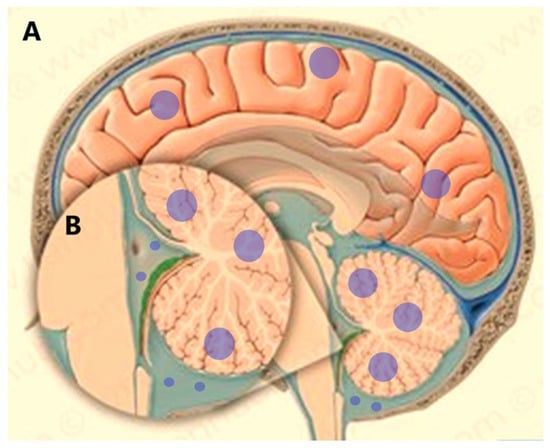

4. Leptomeningeal Dissemination

- Subirá, D.; Serrano, C.; Castañón, S.; Gonzalo, R.; Illán, J.; Pardo, J.; Martínez-García, M.; Millastre, E.; Aparisi, F.; Navarro, M.; et al. Role of flow cytometry immunophenotyping in the diagnosis of leptomeningeal carcinomatosis. Neuro-Oncol. 2011, 14, 43–52. [Google Scholar] [CrossRef] [PubMed]

- Pan, Z.; Yang, G.; He, H.; Yuan, T.; Wang, Y.; Li, Y.; Shi, W.; Gao, P.; Dong, L.; Zhao, G. Leptomeningeal metastasis from solid tumors: Clinical features and its diagnostic implication. Sci. Rep. 2018, 8, 10445. [Google Scholar] [CrossRef]

- Pellerino, A.; Brastianos, P.; Rudà, R.; Soffietti, R. Leptomeningeal Metastases from Solid Tumors: Recent Advances in Diagnosis and Molecular Approaches. Cancers 2021, 13, 2888. [Google Scholar] [CrossRef]

- Milojkovic Kerklaan, B.; Pluim, D.; Bol, M.; Hofland, I.; Westerga, J.; van Tinteren, H.; Brandsma, D. EpCAM-based flow cytometry in cerebrospinal fluid greatly improves diagnostic accuracy of leptomeningeal metastases from epithelial tumors. Neuro-oncology 2016, 18, 855–862. [Google Scholar] [CrossRef]

- Subirá, D.; Simó, M.; Illán, J.; Serrano, C.; Castañón, S.; Gonzalo, R.; Granizo, J.J.; Martínez-García, M.; Navarro, M.; Pardo, J.; et al. Diagnostic and prognostic significance of flow cytometry immunophenotyping in patients with leptomeningeal carcinomatosis. Clin. Exp. Metastasis 2015, 32, 383–391. [Google Scholar] [CrossRef] [PubMed]